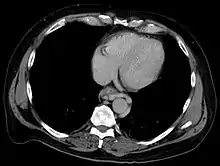

Esophageal varices are extremely dilated sub-mucosal veins in the lower third of the esophagus.[1] They are most often a consequence of portal hypertension,[2] commonly due to cirrhosis.[3] People with esophageal varices have a strong tendency to develop severe bleeding which left untreated can be fatal. Esophageal varices are typically diagnosed through an esophagogastroduodenoscopy.[4]

The upper two thirds of the esophagus are drained via the esophageal veins, which carry deoxygenated blood from the esophagus to the azygos vein, which in turn drains directly into the superior vena cava. These veins have no part in the development of esophageal varices. The lower one third of the esophagus is drained into the superficial veins lining the esophageal mucosa, which drain into the left gastric vein, which in turn drains directly into the portal vein. These superficial veins (normally only approximately 1 mm in diameter) become distended up to 1–2 cm in diameter in association with portal hypertension.

Normal portal pressure is approximately 9 mmHg compared to an inferior vena cava pressure of 2–6 mmHg. This creates a normal pressure gradient of 3–7 mmHg. If the portal pressure rises above 12 mmHg, this gradient rises to 7–10 mmHg.[5] A gradient greater than 5 mmHg is considered portal hypertension. At gradients greater than 10 mmHg, blood flowing through the hepatic portal system is redirected from the liver into areas with lower venous pressures. This means that collateral circulation develops in the lower esophagus, abdominal wall, stomach, and rectum. The small blood vessels in these areas become distended, becoming more thin-walled, and appear as varicosities.